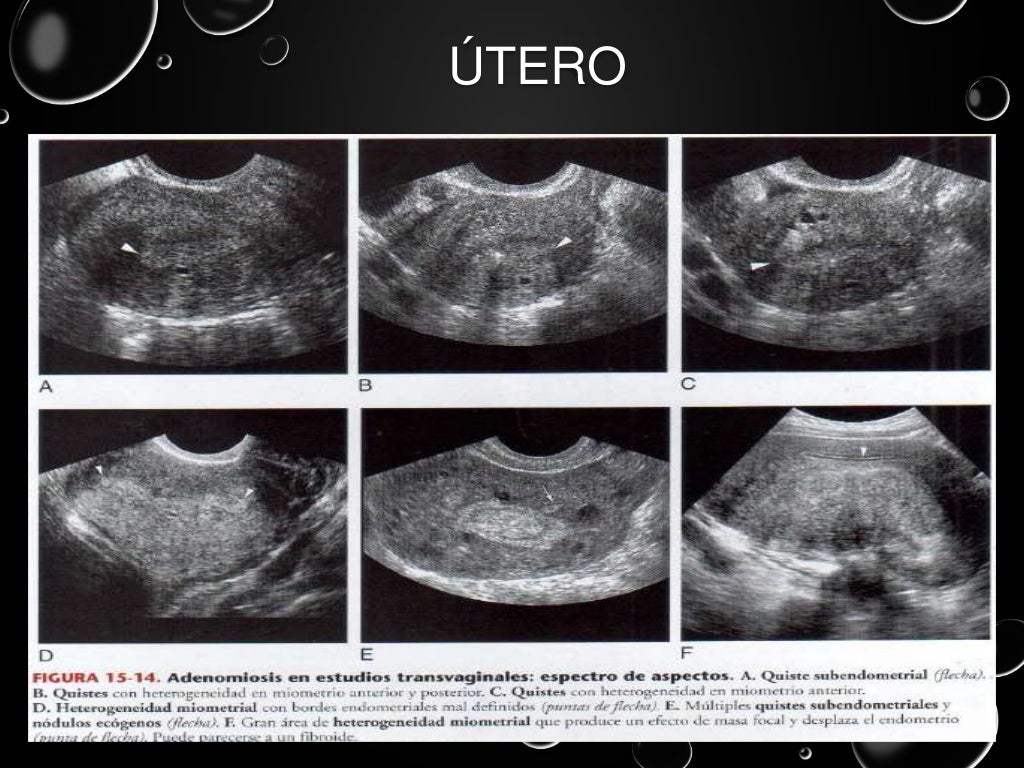

Ultrasonido pelvico

Source: es.slideshare.net